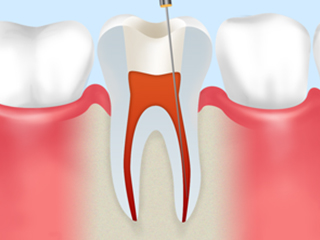

step2

根管内を洗浄し、根管の長さを測ります。